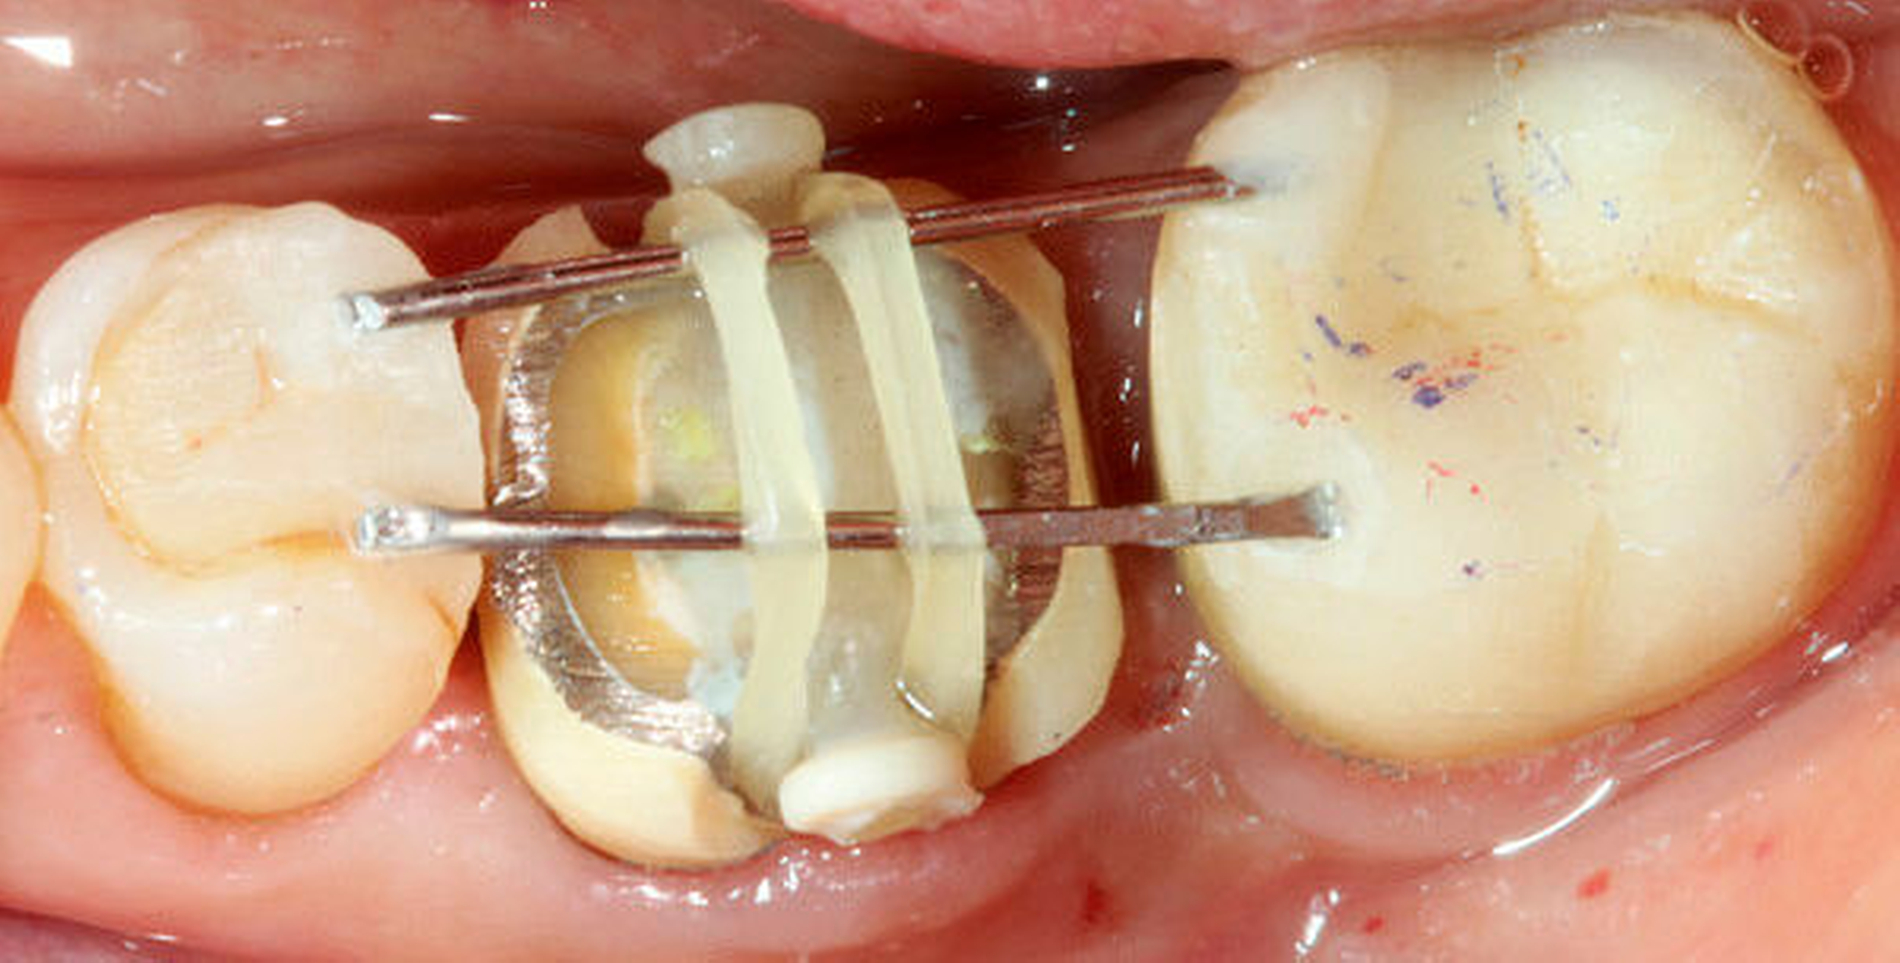

2 | Präparation einer Rille in bukkooraler Richtung zur Positionierung der Extrusionshantel (Fa. Komet) (Abb. 2) |

3 | Adhäsive Fixierung der Extrusionshantel in der Rille (Abb. 3) |

4 | An einem Ende der Extrusionshantel ist bereits eine Retentionslinse angebracht. die zweite Linse muss am gegenüberliegenden Ende adhäsiv fixiert werden |

6 | Adhäsive Fixierung des koronalen 1/3 der ursprünglichen Krone (Frontzahnbereich. Abb. 3) oder der Extrusionsstege (Klammerdraht oder Extrusionssteg Fa. Komet) an den Nachbarzähnen |

7 | Das Extrusionsgummi wird von der oralen Retentionslinse zur vestibulären Linse gespannt (Abb. 3) |